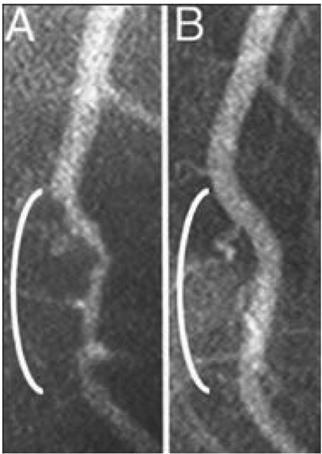

Например, при определенных типах питания можно отсрочить или даже предотвратить опасные для жизни сердечно-сосудистые заболевания. На рентгеновских снимках (рис. 02) можно проследить, как массивные заторы в кровеносных сосудах сами собой растворяются, превращаясь в ничто.

Рис. 0.2. Оба рентгеновских снимка показывают участок левой коронарной артерии, которая снабжает кровью большую часть сердца. Слева (A) можно увидеть больной сосуд (белая «трубка», которая выглядит как ветка и проходит сверху вниз, – обратите внимание на сужение в области белой скобки, как будто трубка сдавлена, что замедляет кровоток). На правой картинке (B) показан тот же самый сосуд после 32 месяцев строгой вегетарианской диеты, при которой пациент питался исключительно растительной пищей. Сужение исчезло, кровоток восстановился, артерия вновь выглядит совершенно здоровой. Болезни сосудов можно не только приостановить, но даже обратить вспять, и все это без хирургического вмешательства и медикаментозного лечения[11].